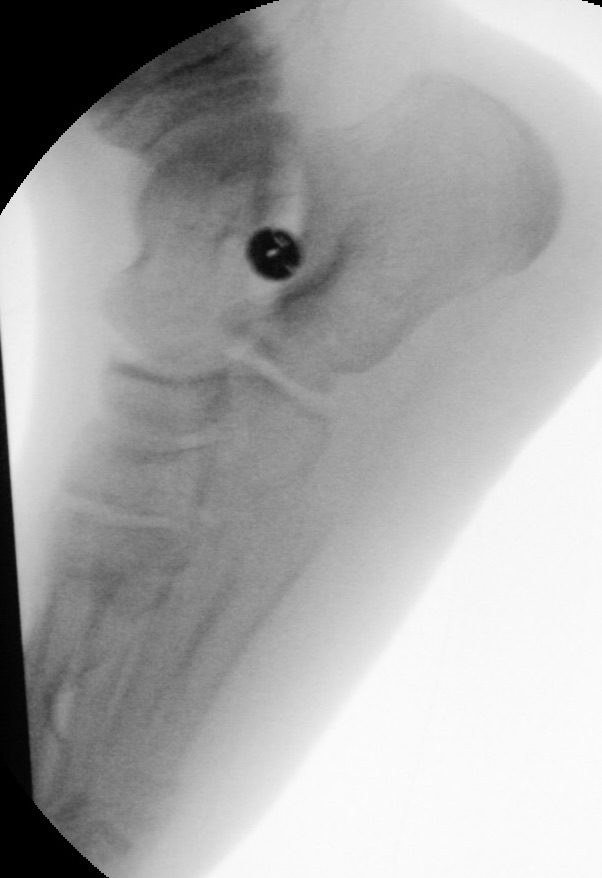

Knick-Senk-Platt-Fuß Korrektur mit dem Canalis Tarsi Spacer

In der Korrektur des schmerzhaften, aber flexiblen Knick-Senk-Fußes oder Plattfußes ist die Schraubenarthrorise mit einem Sinus tarsi oder besser bezeichnet als Canalis tarsi Spacer und alternativ mit einer Calcaneus-Stopp-Schraube seit vielen Jahren ein etabliertes Verfahren und führt zu einer kompletten Korrektur von flexiblen Knick- und Plattfuß-Fehlstellungen (Abb. 7). Die nötige Schnittlänge über dem Sinus tarsi beträgt für beide Verfahren 1 cm.

Abb. 7 a-e: Knick-Senk-Fuß prä- und postoperative Situation (a-b), ventrale und dorsale Ansicht (c-d). Laterale Ansicht des Hautschnittes über dem Sinus tarsi (e).

Zum Lesen der Bildbeschreibung und zur Vollansicht bitte die Bilder anklicken. Bilder: A. Helmers.